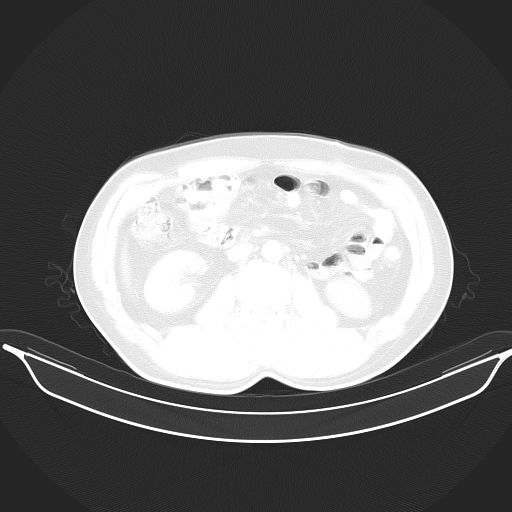

标题: CT25490:男,40岁,体检发现;无其它不适。 [打印本页]

标题: CT25490:男,40岁,体检发现;无其它不适。

考虑右下肺周围性肺癌并肺内多发转移,纵隔淋巴结转移!

支持 !考虑右下肺周围性肺癌并肺内多发转移,纵隔淋巴结转移,(气管前腔静脉后,隆突下,主动脉弓下都有了)

1、均为转移,原发灶不在肺内。2、肺癌肺转移。